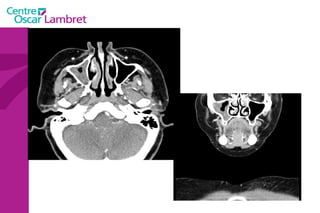

L’appareil respiratoire  Les  fosses nasales  : Les fosses nasales sont deux cavités séparées par une cloison médiane. Elles s'ouvrent vers l’avant par les narines et vers l’arrière, dans le pharynx, par les choanes.  Au niveau des narines, la cloison médiane est cartilagineuse, c’est le cartilage de la cloison.

Le  Pharynx  : Carrefour aéro-digestif qui fait communiquer :  la voie aérienne avec le larynx (extrémité supérieure de la trachée).  la voie digestive avec l’oesophage. Il s’étend verticalement au-devant de la colonne cervicale, en arrière des fosses nasales (rhino-pharynx), de la cavité buccale (oropharynx) et du larynx (laryngo-pharynx).  Il est complètement tapissé par une muqueuse.  L’appareil respiratoire :

Fosses nasales Rhinopharynx Cavité buccale Oropharynx Hypo pharynx Larynx Œsophage trachée